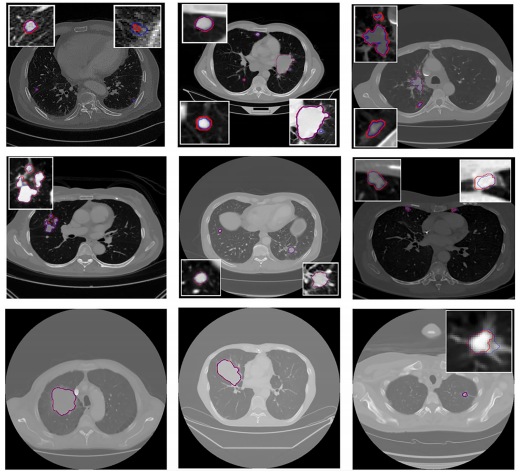

CFPR系统展现出精准分工:XPC在DS-FPX测试中AUROC达99%,专精识别肺外假阳性;3D ResNet-50架构的LVC则在肺内验证中取得89.4%的AUROC。两者级联使整体AUROC提升至90.1%,每例CT平均仅产生2个假阳性,同时保持84.9%的召回率。

这项发表于《European Radiology Experimental》的研究,首次系统解决了多病灶肺癌分割的临床痛点。其创新性体现在三方面:一是采用真实世界多中心数据确保泛化性;二是首创级联分类器策略针对性处理不同来源的假阳性;三是实现全病灶负荷的精准量化。尽管在肺门区和纵隔附近仍存在漏诊(如Fig.7所示案例),但该方法已超越Swin-UNet等对比模型,为肺癌精准诊疗提供了新范式。未来通过纳入更多罕见病灶亚型和扩大无病灶样本验证,将进一步推动该技术的临床转化。